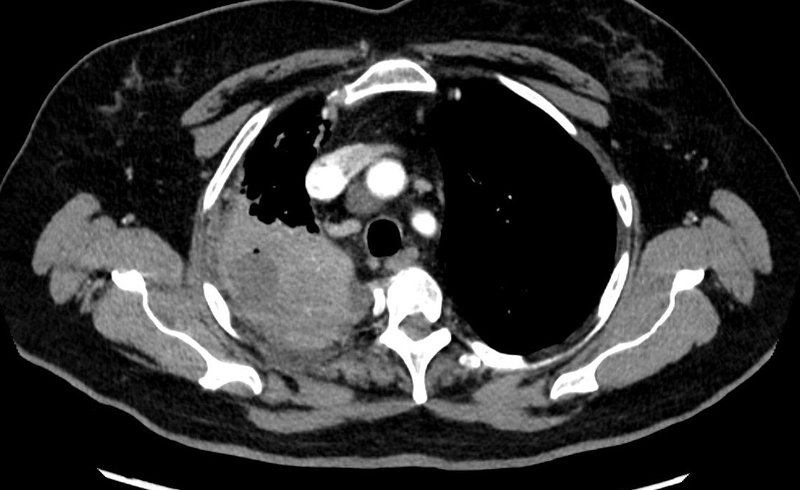

Ngay khi có biểu hiện nghi ngờ, bệnh nhân cần đến cơ sở y tế để được chụp X-quang hoặc chụp CT phổi, kết hợp xét nghiệm máu - đờm để xác định ổ áp xe và mức độ tổn thương phổi.